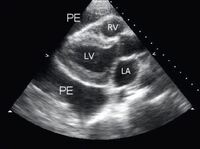

Apical 4-chamber view of a 2-dimensional echocardiogram of a patient with tuberculous pericardial effusion; LA = left atrium, LV = left ventricle, Per eff = pericardial effusion; RA = right atrium, RV = right ventricle

From: George S, Salama AL, Uthaman B, et al. Heart. 2004; 90:1338-1339

Parasternal long-axis view of a pericardial effusion (PE); LA = left atrium, LV = left ventricle, RV = right ventricle

From the collection of Dr Rajdeep Khattar